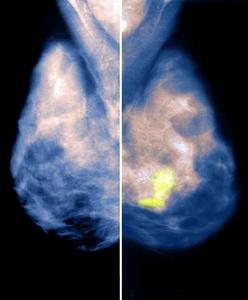

乳房攝影術(英語: Mammography)是利用低劑量(約為 0.7毫西弗)的X光檢查人類(主要是女性)的乳房,它能偵測各種乳房腫瘤、囊腫等病灶,有助於早期發現乳癌,並降低其死亡率。除了影像檢查之外,自我檢查和醫師觸診都是日常乳房保養的重要一環。有一些國家提倡年長(一般為45周歲以上)的女性定期(間隔從一年到五年不等)乳房攝影,以篩檢出早期的乳癌。因為這種檢查的X射線輻射致癌的可能性是很多年以後才出現,如果45-50歲以後再篩查,因接受這種輻射而致癌對人的期望壽命影響極為有限。但對於有BRCA1/BRCA2突變的人,則要格外注意,因為低劑量輻射對基因突變者影響仍然很大。

乳房攝影術一如其他X光檢查,是以游離性輻射穿透人體成像,由放射科醫師分析影像是否有異常。雖然不斷改良,乳房攝影術在醫學界依舊累積了不少反對聲浪,尤其針對它偏高的誤判率與檢查中所用到的輻射線。 乳房攝影術的 偽陰性率(有癌症而未檢出)至少有 10%,部分是因為小腫瘤被緻密的組織遮掩,而且攝影時腫瘤的影像會和大量的正常組織重疊,不易分辨。此外,也有少數患者出現 偽陽性(有異常,但非癌症)。

縱然如此,乳房攝影術用於篩檢早期乳癌仍扮演重要角色。它能在患者或醫師摸到腫瘤前就發現腫瘤,甚至可比觸診早兩年。美國醫學會(AMA)和許多醫學會均建議40歲以上的女性每年做一次乳房攝影術,因為研究證實每年篩檢可早期發現乳癌,而早期的乳癌大多可以根治,同時更有機會保留乳房。

現在已有醫師在著手開發更好的乳癌篩檢方法,並增進乳癌與其他非癌性乳房病灶的鑑別率。研發中的新科技包括 電腦輔助偵測系統(CAD, computer-aided detection)與 數碼式乳房攝影術。後者也稱為全域數碼式乳房攝影術(FFDM, full-field digital mammography),是用固態感光元件取代底片,將X光轉換為電子信息,原理類似數位相機。所得的影像可以在螢幕上顯示,也可以沖印在類似傳統乳房攝影術的底片上。從患者的立場而言,數碼式乳房攝影術和傳統式幾乎沒什麼兩樣。

電腦輔助偵測系統(CAD)是分析數碼式的乳房影像(可以來自數碼式攝影,或從傳統底片掃描而得),由軟體針對影像搜尋可能是腫瘤的陰影、腫塊或鈣化點。軟體會將可疑區域做上記號,提醒放射科醫師詳加檢視。